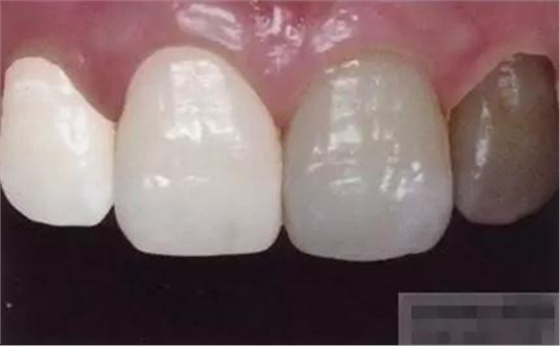

【檢查】12,11,21,22,均行玻璃離子充填,各牙不同程度部分充填物脫落,探(—),叩(—),冷刺激無反應(yīng),無松動(dòng),牙齦顏色粉紅,質(zhì)地堅(jiān)實(shí)而有彈性,點(diǎn)彩正常,牙結(jié)石(—);牙髓活力測試無反應(yīng)。

【診斷】12,11,21,22牙體缺損